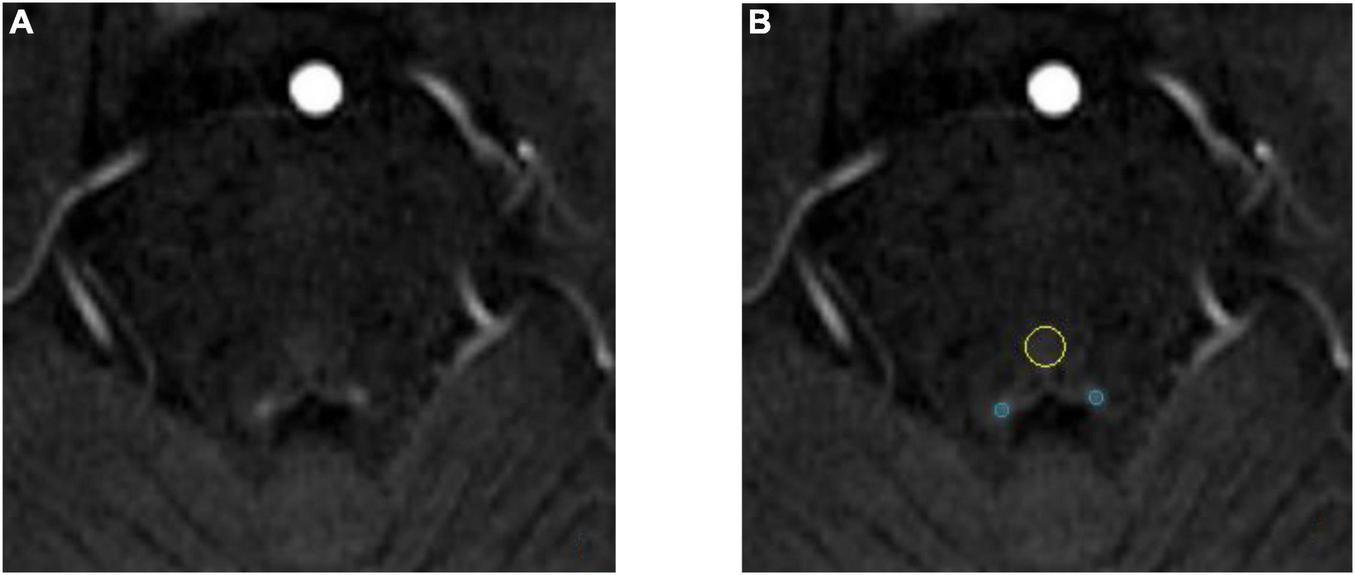

The calculation of the locus coeruleus

The anatomical location of the LC is shown in Figure 3. As shown in the Figure 4A, on the scanned axial map of the pons, the LC shows the anterior dorsum of the pons and two small hyperintense areas around the base of the fourth ventricle. By virtue of the anatomical position, the slice on which LC showed the maximum signal intensity was determined LC. By using the ImageJ software,1 a circular region of interest (ROI) with an area of 1 mm2 was drawn on the brightest pixels of the LC on the left and right sides, respectively, and the average signal intensities were calculated from the LCs on both sides. Using the signal intensity of the pontine tegmentum (SIPT) as a reference area, it was calculated using a circular ROI of 10 mm2 (Figure 4B). In this study, the division of the regions of interest and the calculation method of locus coeruleus signal contrast ratios (LC-CRs) were as follows: The circular ROI was fixed at each pons, that is, at approximately the same distance from the LC ROIs on both sides, which was performed based on previous studies. Signal intensities of the LC (SILCs) were measured on both sides, respectively, followed by the calculation of the average SILC. Finally, the LC signal contrast was calculated with the formula: LC-CRs = (SILC-SIPT)/SIPT.

FIGURE 4

Schematic diagram of locus coeruleus (LC) signal and the region of interest (ROI) delineation. Both images are from the same 71-year-old healthy control. (A) The locus coeruleus (LC) exhibits relatively high signal after NM-MRI scanning. (B) Schematic diagram of the region of interest (ROI). The blue circle is the LC and the yellow circle is the pontine tegmentum (PT) reference area.